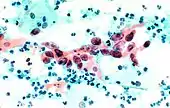

The stain should result in cells that are fairly transparent so even thicker specimens with overlapping cells can be interpreted.[2] Cell nuclei should be crisp, blue to black on color[12][13] and the chromatin patterns of the nucleus should be well defined. Cell cytoplasm stains blue-green and keratin stains orange in color.[13][5]

Eosin Y stains the superficial epithelial squamous cells, nucleoli, cilia, and red blood cells.[2] Light Green SF yellowish confers a blue staining for the cytoplasm of active cells such as columnar cells, parabasal squamous cells, and intermediate squamous cells.[14] Superficial cells are orange to pink, and intermediate and parabasal cells are turquoise green to blue.[12]